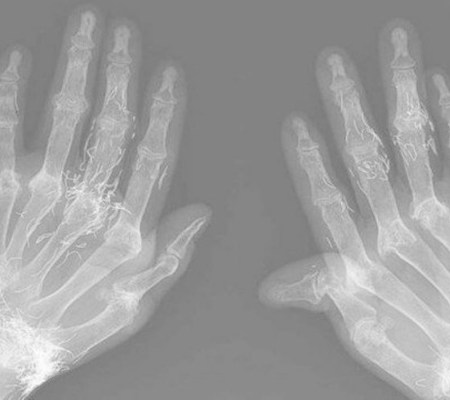

Um exame de raio-X de uma paciente de 58 anos na Coreia do Sul apresentou um resultado incomum: vários traços de ouro nas mãos da mulher, que sofre de artrose. As informações são do Extra.

A imagem foi publicada em um relato na conceituada revista médica "New England Journal of Medicine". A paciente foi a uma clínica reumatológica queixando-se de fortes dores nas juntas. Ela apresentava deformações nas mãos e nos pés.

A paciente foi submetida a inúmeras sessões de acupuntura com fios de ouro. Nela, pequenos pedaços de fio de ouro estéril são inseridos no corpo usando uma agulha de acupuntura.

De acordo com Young-Bin Joo e Kyung-Su Park, autores do relato, a prática é usada há muito tempo no extremo oriente da Ásia. O ouro, além do procedimento com as agulhas da acupuntura, pode também ser injetado ou administrado por via oral.

Os autores disseram que a acupuntura com fios de ouro não fez o quadro da paciente piorar, mas ele também não melhorou com a prática.